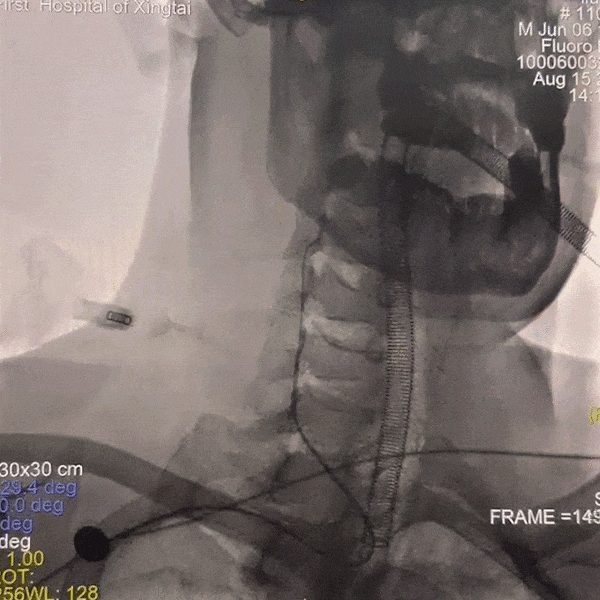

手术过程

通路建立:经桡造影显示Ⅲ型弓,病变为右侧颈内动脉C4段动脉瘤,患者桡动脉纤细不适合经桡治疗,故选择经股动脉应用赛诺神畅APEX TRA GC™5F-130 SIM2导引导管超选右颈,同轴长鞘建立通路。

动脉长鞘怎么置入一技之“长”丨经桡及经股困难入路应用赛诺神畅APEX TRA GC™导引导管建立通路病例合集_https://www.jmylbn.com_新闻资讯_第20张

Ⅲ型弓

动脉长鞘怎么置入一技之“长”丨经桡及经股困难入路应用赛诺神畅APEX TRA GC™导引导管建立通路病例合集_https://www.jmylbn.com_新闻资讯_第21张

SIM2导管成袢

动脉长鞘怎么置入一技之“长”丨经桡及经股困难入路应用赛诺神畅APEX TRA GC™导引导管建立通路病例合集_https://www.jmylbn.com_新闻资讯_第22张

超选入无名动脉

跟进长鞘至右侧颈内动脉。